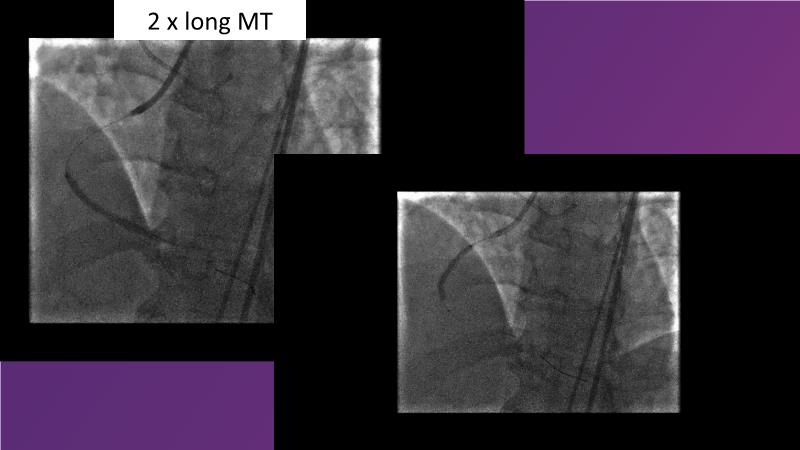

Sirolimus-coated balloon: expanding the scope of indications for complex coronary artery disease treatment

Watch this session to gain case-based insights on using DCBs in complex settings. Learn valuable tips and tricks for optimal DCB application, including the best timing and situations for their use. Discover how to effectively implement a hybrid strategy that combines DES and DCB when needed.

- To get a case based experience on how to use a DCB in complex settings